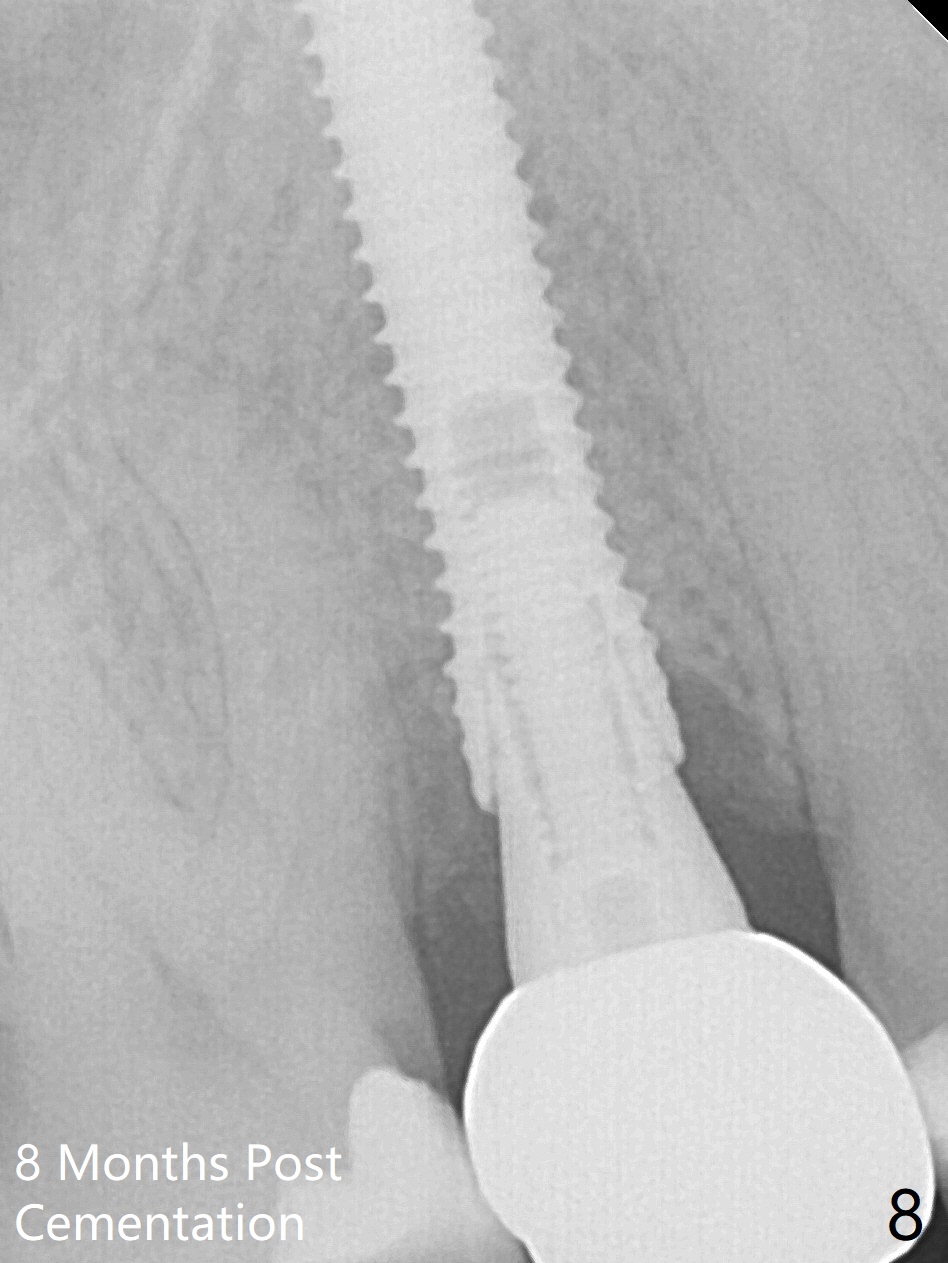

When the tooth #4 with vertical root fracture (Fig.1) is extracted, the buccal plate is found to be lost. The lowest point of the defect is shown as black dashed line in Fig.2 (yellow dashed line: sinus floor). After use of 2.5 mm reamer for 21 mm (buccal gingival level) and 3.0 mm reamer for ~17 mm, a 3.8x15 mm dummy implant is placed with 30 Ncm and 1.85 mm apical space (Fig.3 pink outline). A 3.8x18 mm (definitive) implant is placed with <40 Ncm with the implant plateau apical to the lingual crest (Fig.4,5). The buccal plate defect is repaired by Vanilla Graft (Fig.6 *) before and after insertion of a 4.5x4(3) mm abutment. The buccal plate defect seems to being repaired 4 months postop (Fig.7). Occlusal wear suggests bruxism, which is also associated with the root fracture. Night guard is recommended. The defect repair is close to completion 8 months post cementation (Fig.8). The crown/abutment is found to be loose 1 year 4 months post cementation and retightened without checking whether there is clinical 2nd DO caries of #3 (Fig.9, "sensitive to water pik"). A few days later, DO composite is being removed. It is difficult to determine whether the 2nd DO caries or gap has been removed with the neighboring crown in place. When the crown/abutment is removed and gingival retractions are inserted, there is no decay. The gap is removed. With Toflemire in place, the crown/abutment is reseated and hand tightened; after packable composite, the crown/abutment is removed, there is no more DO gap.